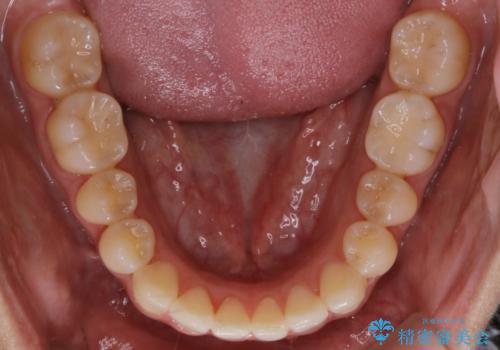

【非抜歯】部分矯正でも治る 前歯の反対咬合

- 前歯にガタつきを主訴にご来院されました。

奥歯の嚙み合わせに問題がほとんどみられなかったため、インビザライン ライトパッケージでの部分矯正を行うこととなりました。

今回のケースでは奥歯の噛み合わせに問題がほぼみられなかったため、前歯の位置のみに焦点を当て部分矯正を行いました。

適応されるケースが限られるものの、適応であった場合の治療期間は全体矯正と比べると格段に短くなり、費用も抑えられます。